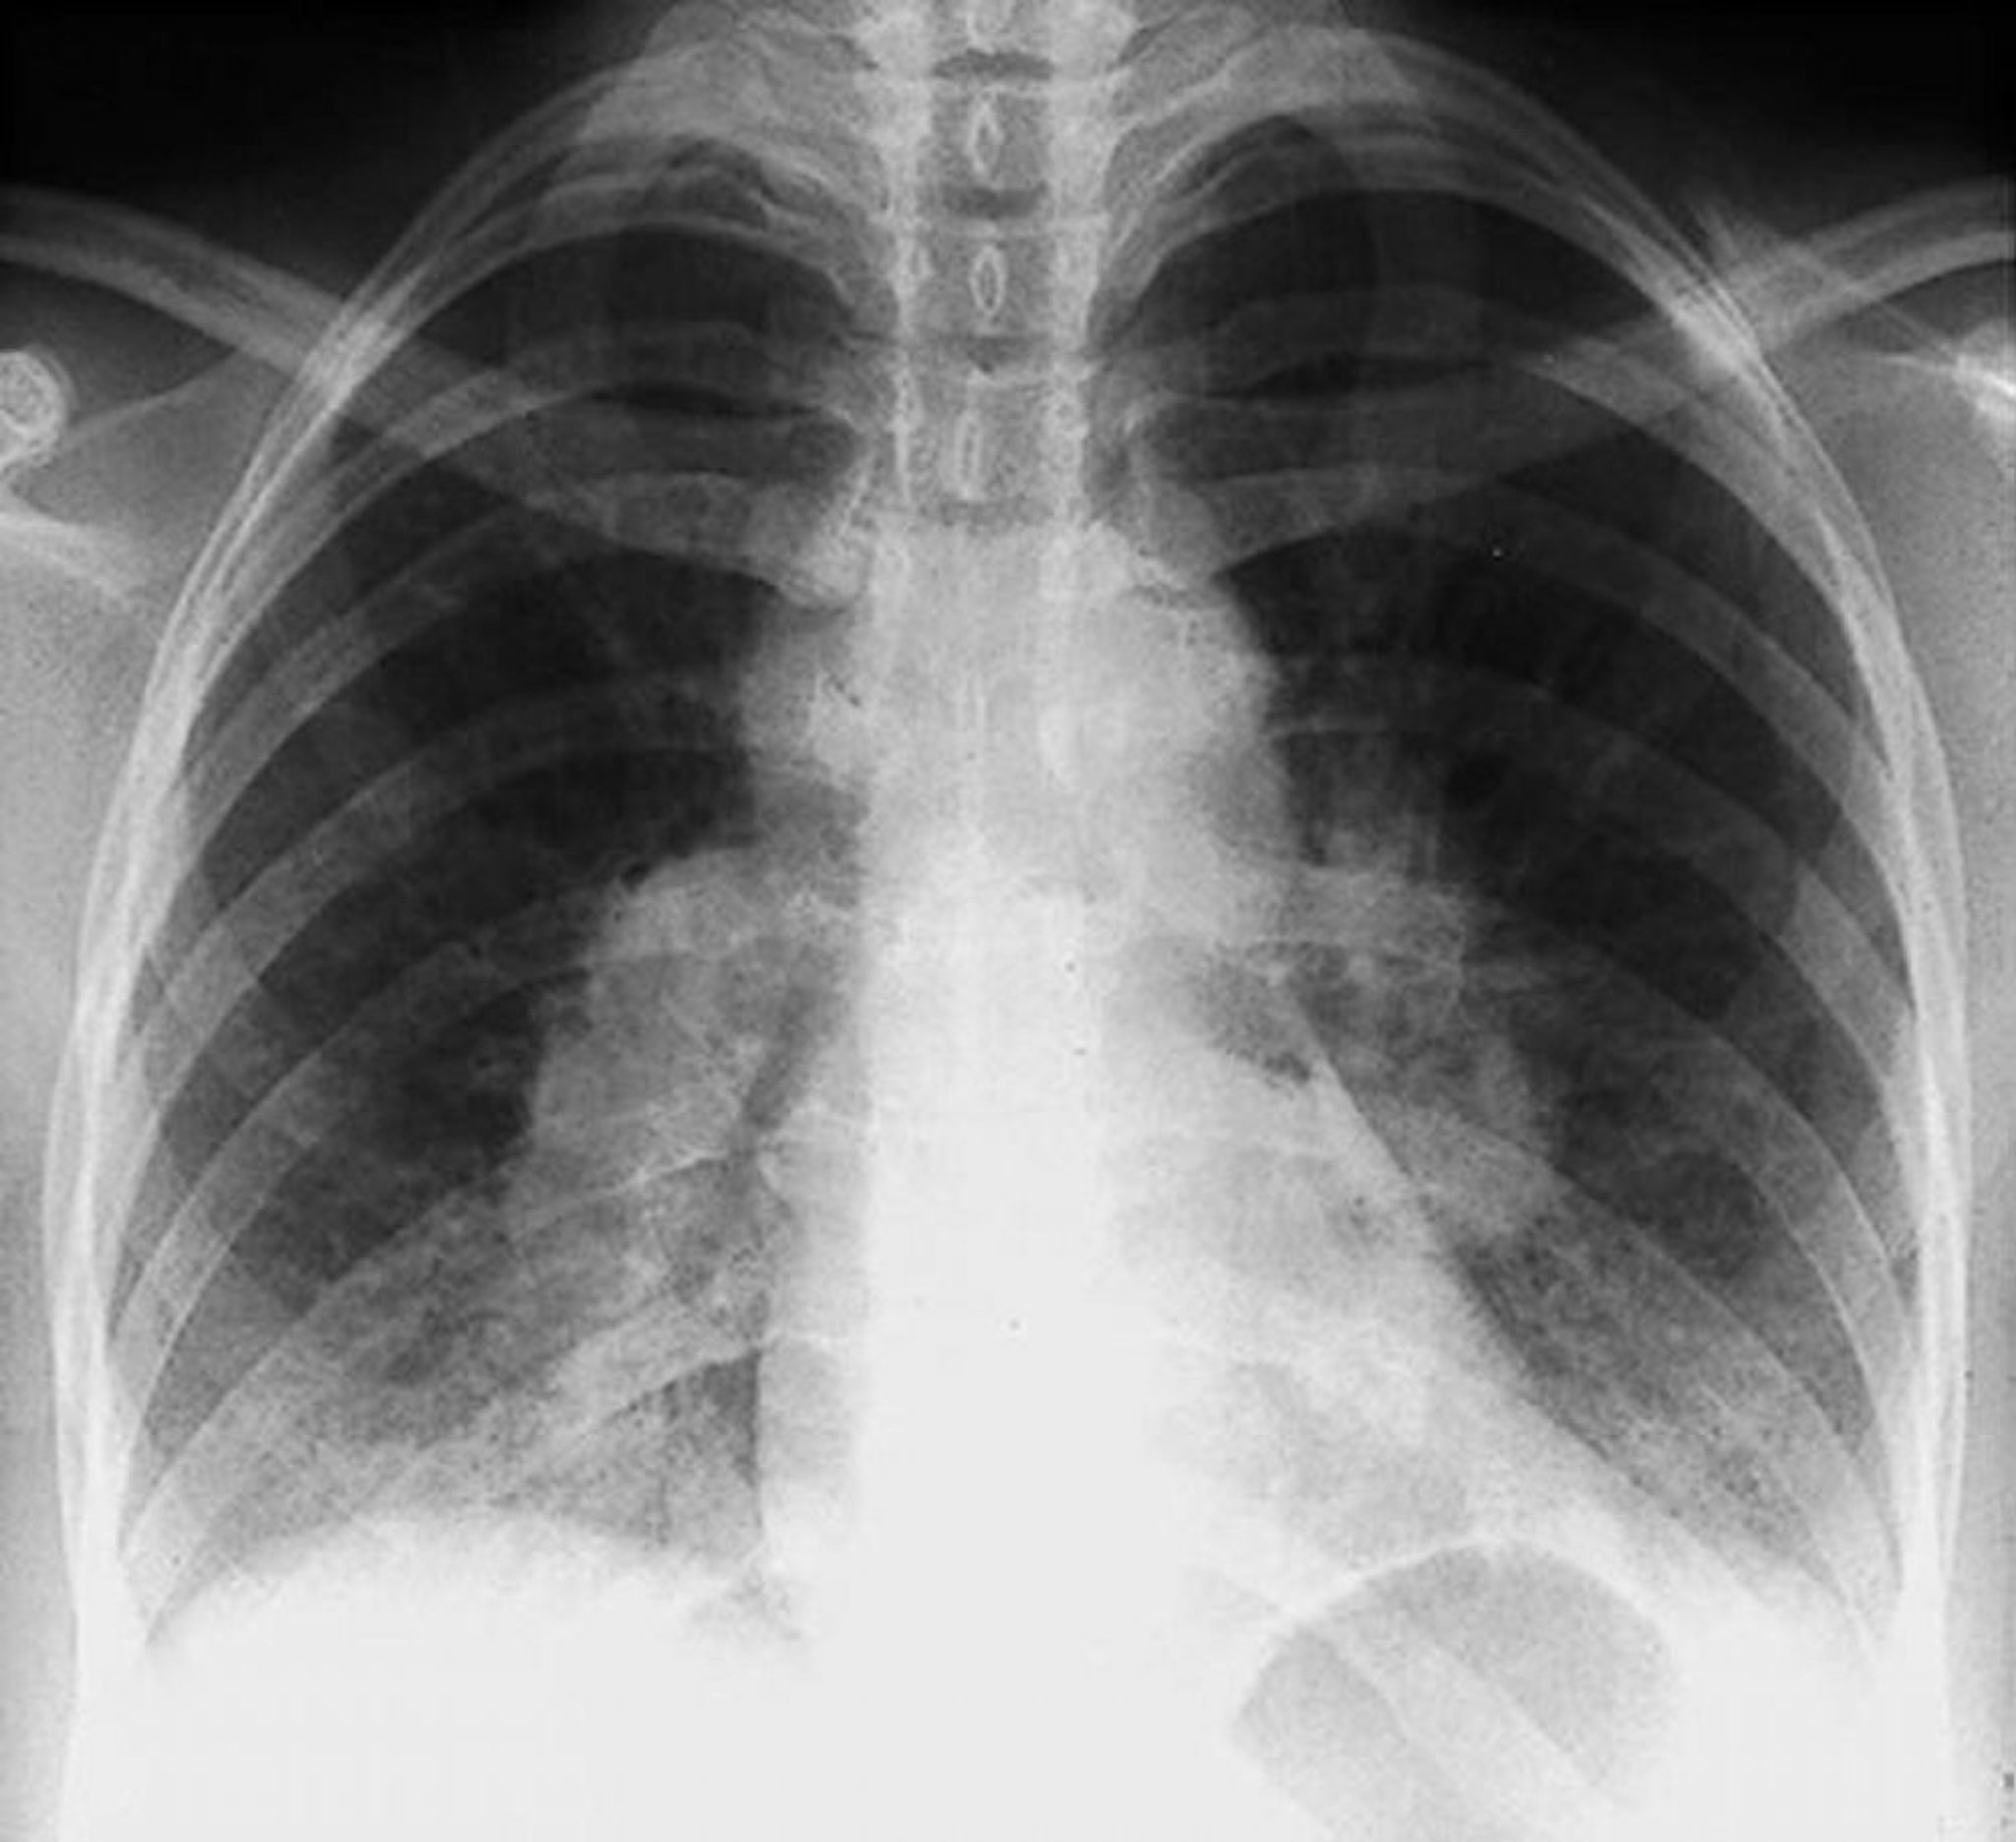

Sarcoidose (estágio I)

Adenopatia hilar bilateral na sarcoidose em estágio I.

By permission of the publisher. De Tanoue L, Elias J. In Bone's Atlas of Pulmonary and Critical Care Medicine. Edited by J Crapo. Philadelphia, Current Medicine, 2005.